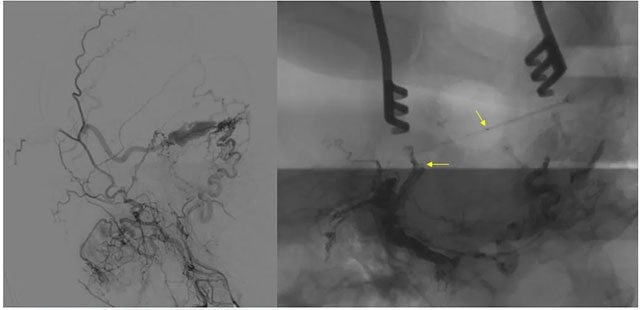

经左侧股动脉以单弯造影管超选至左侧颈总动脉造影明确静脉穿刺点入路,予以穿刺针穿刺成功后造影明确在位,随后 Echelon 10微导管到位横窦,填入一枚弹簧圈做塞子,造影明确位置后,缓慢注入 Onxy18胶 5毫升,铸胶弥散良好,通过静脉逆向弥散至部分供血动脉内。复查造影,见瘘口完全被栓塞,引流静脉消失,手术成功。

术后患者临床症状消除,精神矍铄,现正在康复中。

▲ 术后影像